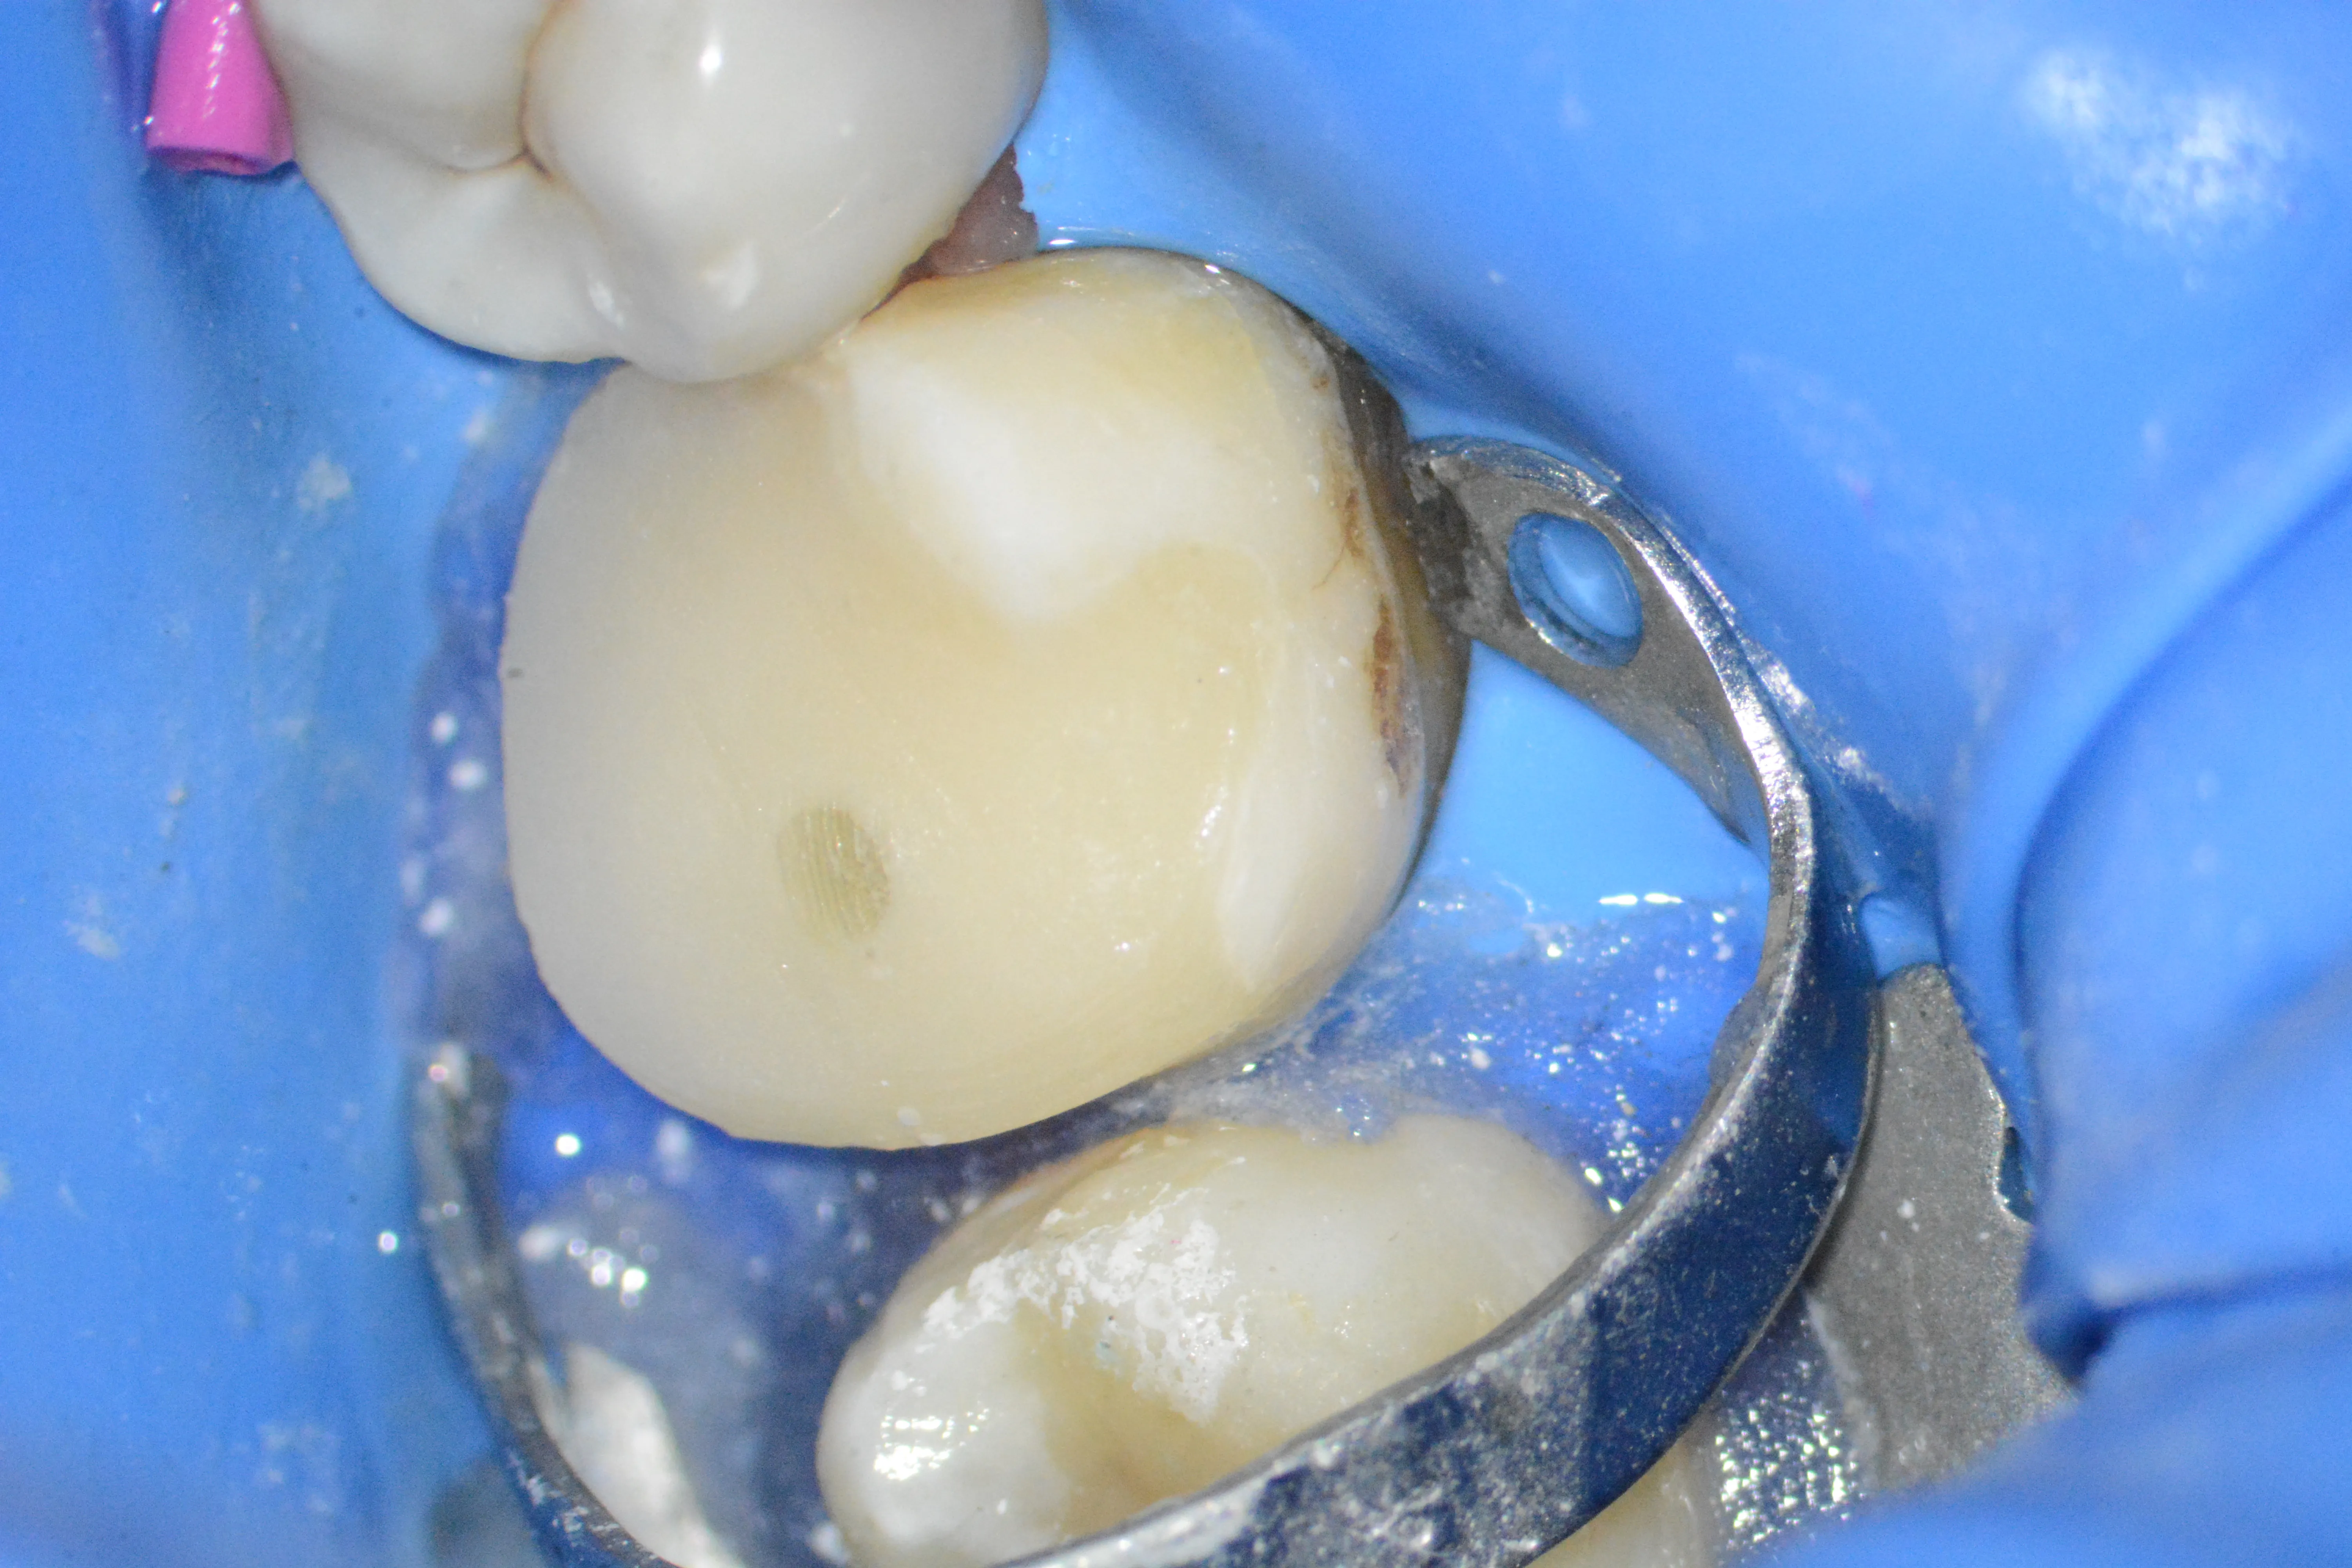

1 – Situație clinică inițială